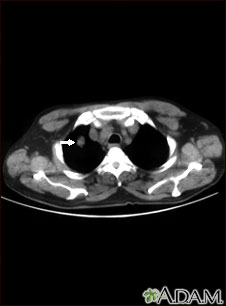

This CT scan shows a single lesion (pulmonary nodule) in the right lung. This nodule is seen as the light circle in the upper portion of the dark area on the left side of the picture. A normal lung would look completely black in a CT scan.